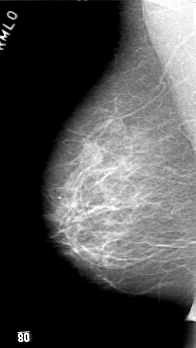

D_4033_1.RIGHT_MLO

RIGHT_MLO LINES 5206 PIXELS_PER_LINE 2926 BITS_PER_PIXEL 12 RESOLUTION 43.5 NON_OVERLAY